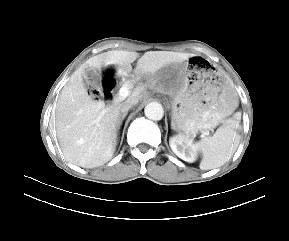

标题: CT19533:病变来源于哪?

患者,男,发现上腹部包块两月余。

病变位于肝胃间隙,实际就是位于小网膜囊(左肝下后间隙),呈轻度不均匀性强化,腹腔内及腹膜后见多发肿大淋巴结。所以我考虑肝胃间隙恶性胃肠间质瘤并淋巴结转移。

肝胃韧带内及腹膜后可见多发增大的淋巴结影,首先考虑转移.